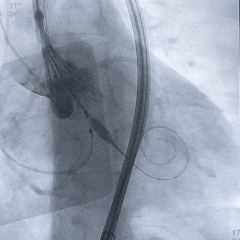

工作位造影:无冠窦侧瓣下2mm左右,瓣膜形态直筒

左冠切线位,可见左冠开口无遮挡

多角度观察,确认瓣膜稳定

脱钩后造影,瓣膜位置可,几乎无瓣周漏

左冠切线造影,确认冠脉无遮挡